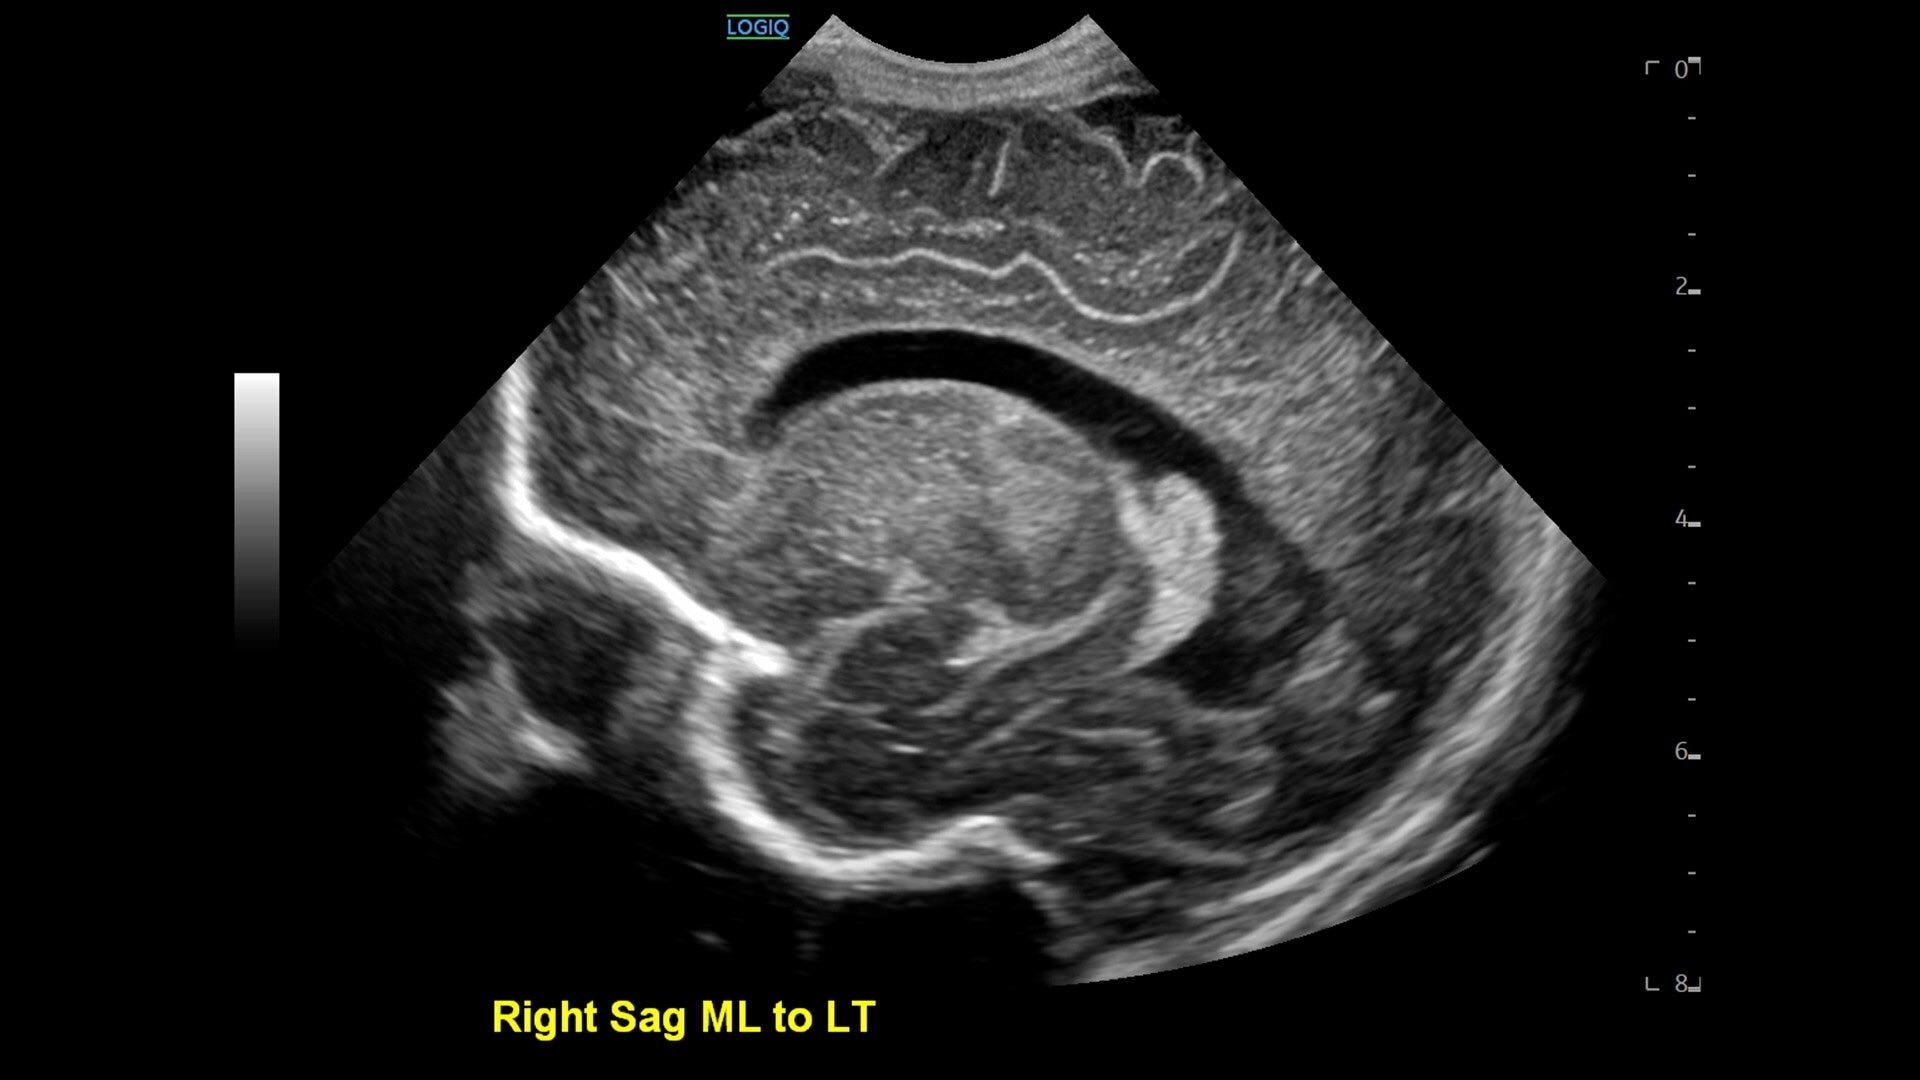

• cSound™ Architecture delivers exceptional clarity and resolution from near field to depth—with all pixels in focus

• Advanced flow modes give you the flexibility, from large vessels to fine microvascular detail, to visualize blood flow with precision

• Ultrasound-Guided Fat Fraction (UGFF) quantifies liver steatosis as a percentage, supporting detection and management - especially for patients with Metabolic Dysfunction-Associated Fatty Liver Disease (MAFLD)

• 2D shear wave elastography with quality map provides quantitative insight into tissue elasticity—helping you assess different structures with confidence

• Contrast-Enhanced Ultrasound (CEUS) delivers clear visualization of tissue structure and lesion vascularity—empowering confident lesion detection and characterization